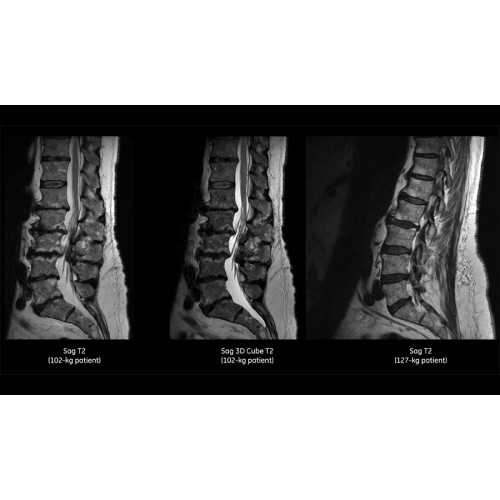

Система SIGNA Pioneer воплощает поразительные достижения в области визуализации. Передовая технология Total Digital Imaging (TDI) позволяет добиться большей четкости изображений и на четверть повысить соотношение сигнал/шум.

• Технология Digital Surround Technology (DST) — это новая технология объемной оцифровки данных, объединяющая сигналы от каждого элемента катушки. Прекрасное соотношение сигнал/шум и чувствительность поверхностных катушек в сочетании с превосходной однородностью и высокой проникающей способностью встроенной радиочастотной катушки — все это позволяет создавать качественные изображения не только позвоночника, но и всего тела.

Помимо технологии 97 РЧ-каналов, SIGNA Pioneer использует магнит 3.0Т высокой однородности, предназначенный для повышения качества визуализации во всех областях, а также закладывающий прочный фундамент для долгосрочных инвестиций и роста клинических возможностей.